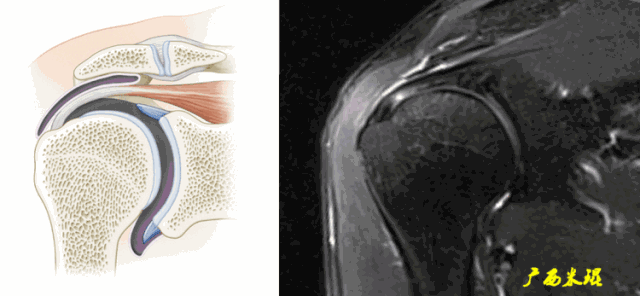

MRI对肩关节伤病诊断的重要性不言而喻,肩袖的MRI诊断首先必须要熟悉肩袖的解剖、功能解剖以及其损伤的病理解剖,其次MR本身的知识必不可少。

肩袖(Rotator cuff)损伤由Smith于1834年发现并命名,指组成肩袖的冈上肌、冈下肌、肩胛下肌和小圆肌的损伤。肩袖是以上4条肌腱共同组成的功能复合体,呈一个袖套状包绕肱骨头,维持盂肱关节的稳定,同时提供肩关节活动时所需的动力。

冈上肌和冈下肌在肱骨大结节上有共同止点,冈上肌和肩胛下肌在结节间沟处共同包绕肱二头肌长头腱。这样紧密的关系预示着肩袖的某一部分组织发生病变一般都会波及其余的肩袖组织,也是我们MRI阅片中必须要注意的。

正常肩袖的MRI表现

各个序列肩袖均表现为均匀的低信号,是肌腱的延续。